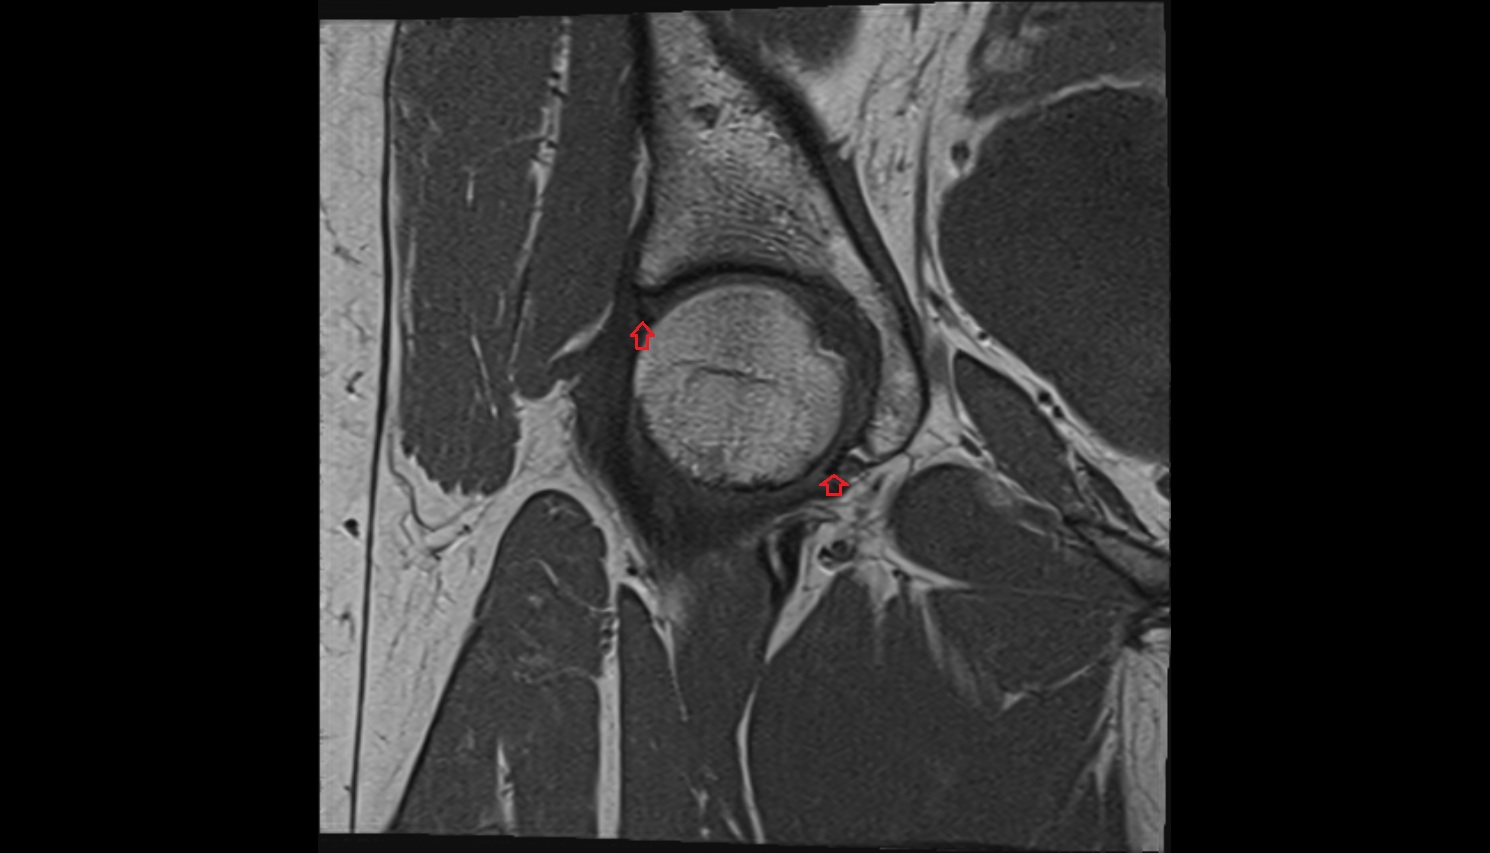

- Knee Joint

- Medial meniscus

- Lateral meniscus